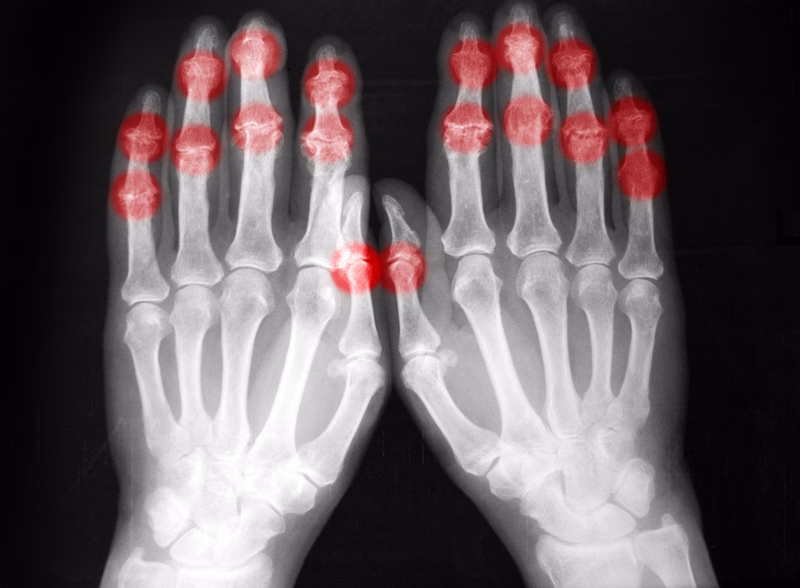

African Health News Radiography demand surges amid manpower shortage and rising complications The demand for medical imaging procedures has led to a surge in diagnostic investigations, resulting in rising complication trends and […] December 1, 2025